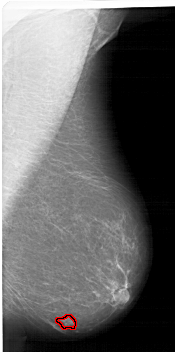

A_1422_1.RIGHT_CC

FILE: A_1422_1.RIGHT_CC.OVERLAY

TOTAL_ABNORMALITIES 1

ABNORMALITY 1

LESION_TYPE MASS SHAPE IRREGULAR MARGINS ILL_DEFINED

ASSESSMENT 4

SUBTLETY 1

PATHOLOGY BENIGN

TOTAL_OUTLINES 1

BOUNDARY